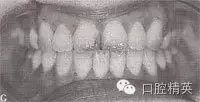

圖9-42 開頜病例矯治后的咬合像

治療:減右上4,右下4,左上6后,直絲弓矯治器+MEAW技術(shù)矯治,經(jīng)2年半治療,擁擠、開頜及反頜畸形得以矯治,咬合關(guān)系良好。